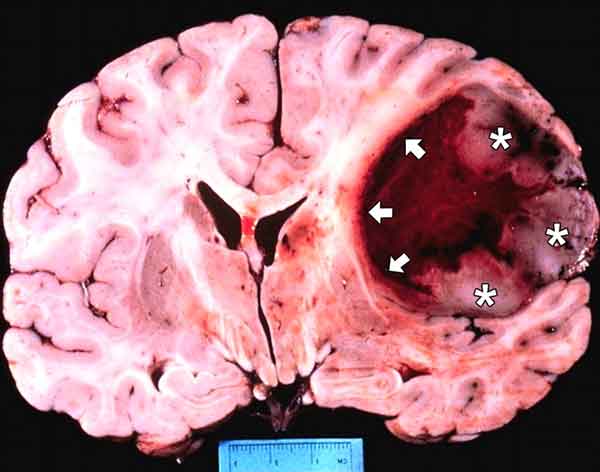

Un glioblastoma di quarto stadio, uno dei tumori più maligni, quello che uccide il numero maggiore di persone sotto i 40 anni. Tuttavia un ulteriore intervento chirurgico, seguito da radioterapia, è stato ri-solutivo. E mentre era in cura ha ... Return Document